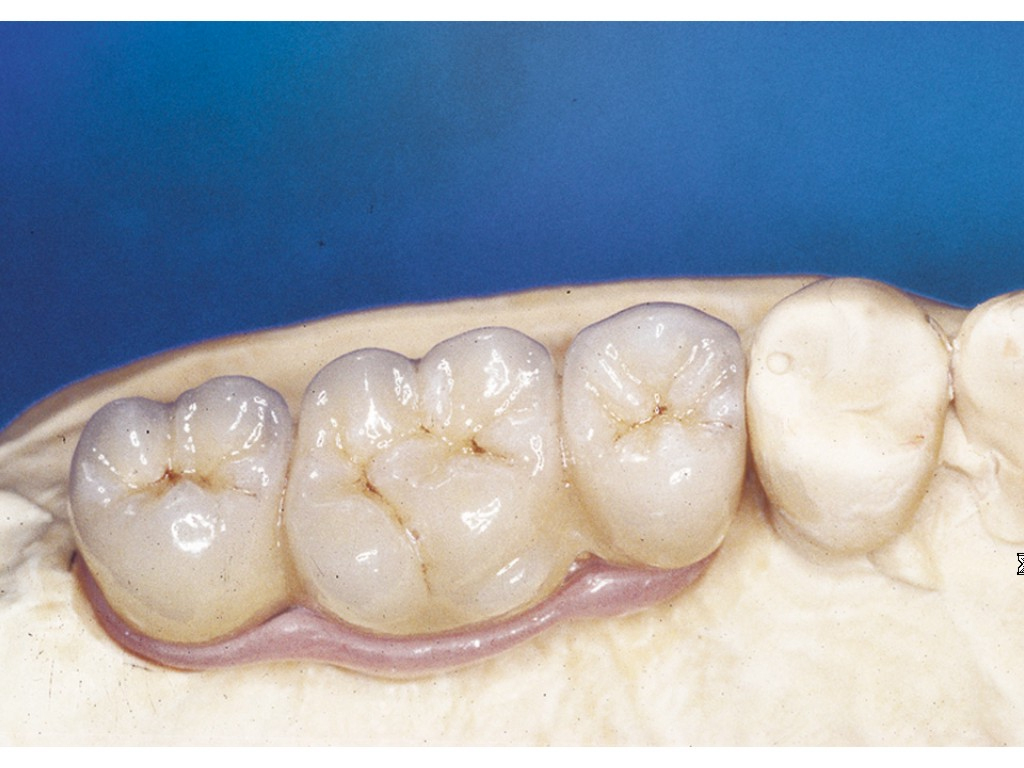

V případě chybění většího počtu zubů v postranních úsecích čelistí je možné ošetření pomocí implantátů, které nahradí ošetření pomocí snímacích náhrad kotvených na zbývajících zubech nebo patře.

Podmínkou je opět dostatečné množství kosti.

Protetické řešení může být pomocí můstku, který je kotvený na implantátech nebo pomocí jednotlivých korunek na implantátech.

V zásadě je možné do těchto můstků zařadit i přirozené zuby, zejména pokud je potřeba tyto zuby ošetřit proteticky – korunkami. Korunky nebo můstky mohou být na implantáty nacementovány nebo přišroubovány.

Zdravé zuby zůstanou zachovány a přitom náhrady jsou pevné, jako na vlastních zubech